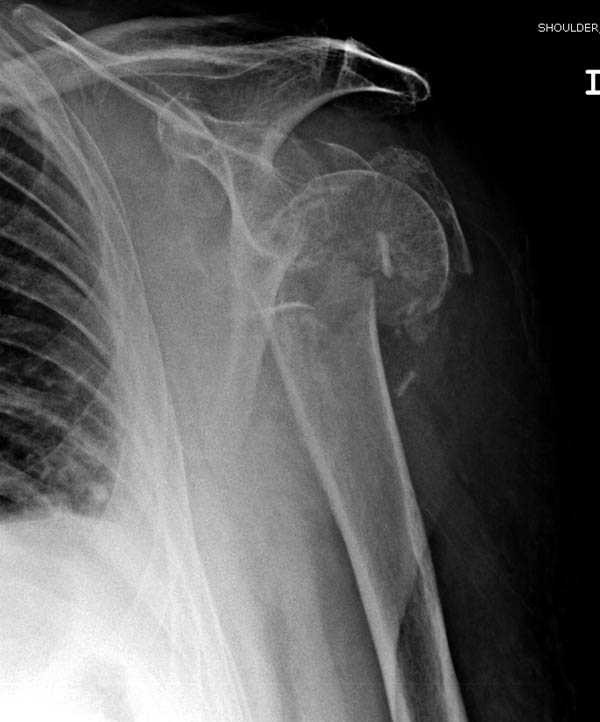

Здесь пример открытой репозиции 57 летнего с переломом плеча (1,2) смещение обнаружено на интероперационном снимке. При нормальной прямой проекция (3) угловое смещение обнаружили в аксиальной проекции (4)

После устранения смещения пластина установлена выше (5,6,7) и финальные снимки (8,9,10)